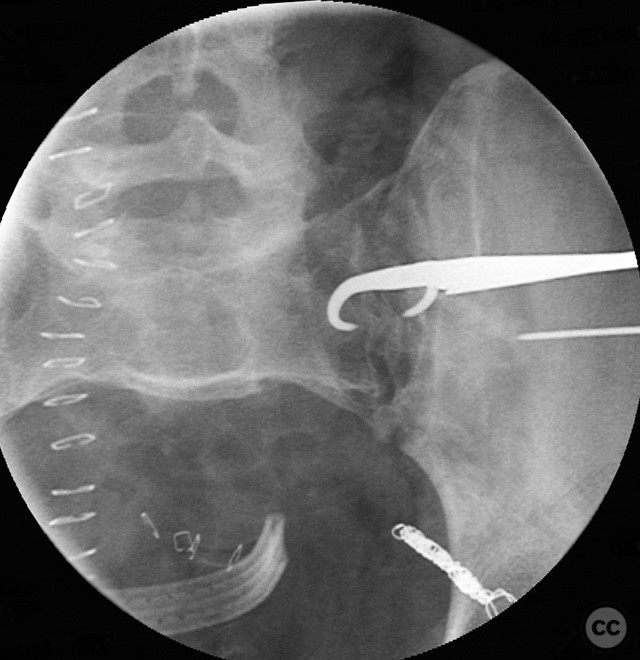

Clinical and radiological findings:  Middle-aged male involved in a motor vehicle accident sustained a complete symphysis pubis (SP) disruption and left sacroiliac (SI)/sacral combination fracture-dislocation (AO/OTA 61-C1.3). The patient presented with an open traumatic posterior pelvic wound. Initial assessment revealed hemodynamic instability requiring urgent laparotomy and subsequent angioembolization for pelvic hemorrhage. Axial CT imaging demonstrated significant displacement of the anterior and posterior pelvic ring, with embolic coils visible post-intervention.

Anatomical surgical approach:  Anteriorly, a low midline infraumbilical incision was made to expose the symphysis pubis, with subperiosteal dissection of the rectus sheath and direct visualization of the disrupted symphysis. Posteriorly, a longitudinal midline approach over the sacrum was utilized, incorporating the traumatic wound for I&D. Deep dissection allowed access to the sacral ala and SI joint. A tenaculum clamp was applied percutaneously to achieve reduction of the sacral/SI fracture-dislocation. Iliosacral screws were inserted percutaneously under fluoroscopic control across the SI joint into S1.